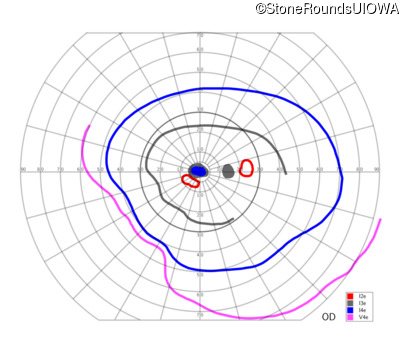

This 52 year old man had normal vision until his mid 30's when he began to have trouble distinguishing colors. the issuing 10 years he had a gradual loss of visual acuity accompanied by increasing photophobia.

| Age at visit: 55 years |

| Age at visit: 58 years |

| Age at visit: 61 years |

| Age at visit: 64 years |